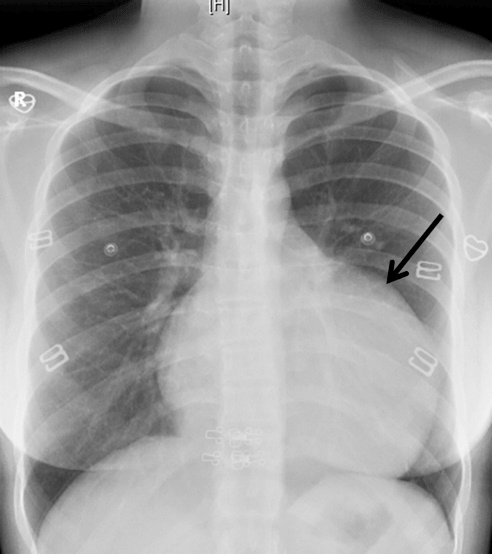

A 22-year-old woman was admitted at our institution in May 2018 with intermittent episodes of chronic atrial fibrillation, angina and dyspnea on exertion New York Heart Association Class-IV. She had three episodes of transient loss of consciousness with no neurological deficits. Notable clinical findings included an intermittently irregular pulse, blood pressure of 90/60 mmHg, cardiomegaly with normal heart sounds and no murmur. The electrocardiogram demonstrated atrial fibrillation, left atrial enlargement, normal axis and voltage. The chest roentgenogram revealed an enlarged cardiac silhouette with a prominent convex bulge of the left upper cardiac border without hilum overlay sign and carinal widening (Figure 1). Transthoracic and transesophageal echocardiogram revealed a giant left atrial aneurysm (8.33 x 7.01 x 4.0 cm) with a wide neck (4.0 cm). The aneurysm extended to the apex of the left ventricle and was entirely intrapericardial and did not show any intraluminal thrombus (Figure 2). The left ventricular diameter and wall motion were within the normal limits. She had moderate dysfunction of the left ventricle (left ventricular ejection fraction=0.35). The interatrial septum and the heart valves were all normal. The visceral layer of the pericardium appeared to be intact.

Figure 1: The posteroanterior chest radiograph reveals a bulge in the location of the left atrial appendage (black arrow).

Therefore, even though rare, if a young patient presents with atrial fibrillation with no other associated cardiac pathologies, a left atrial appendage aneurysm should be ruled out [12, 28]. Physical examination is often unrevealing [1-3, 17-28]. A chest roentogenogram may show a non-specific cardiomegaly with an unusually prominent left heart border [19, 29-31]. Radiologically, a left atrial appendage aneurysm must be differentiated from other diagnoses such as congenital deficit of the pericardium with atrial herniation, mitral valve pathology causing atrial dilatation, juxta position of the atrial appendages, pericardial cyst, mediastinal mass or cardiac tumour [1-3, 19, 29-31]. Transthoracic echocardiography could diagnose left atrial appendage aneurysm accurately only in twenty-four percentage of patients due to limited echo window. However, it is useful in evaluating left ventricular function, abnormal myocardial motion, and valve regurgitation caused by compression of the left atrial aneurysm. Besides, it helps to exclude other cardiac abnormalities [28, 32].